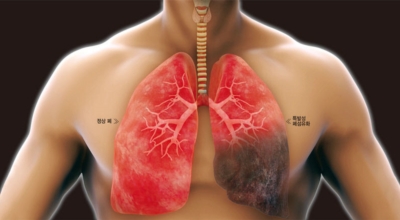

폐렴이란

폐렴은 폐의 세기관지 이하 부위 특히나 폐포에 발생한 염증입니다. 폐렴을 유발하는 병원 미생물은 우리의 생활환경에 존재하고 있고 몸 안에 서식합니다. 폐렴의 가장 흔한 까닭은 미생물인 세균이나 바이러스이고, 드물게 곰팡이에 의한 감염이 있을 수 있습니다.

미생물에 의한 감염성 폐렴 이외에 화학물질이나 구역질물과 같은 찌꺼기의 흡인, 가스의 흡인, 방사선 치료 등에 의해 비감염성 폐렴이 발생할 수 도 있어요. 폐렴구균은 노인을 감염시키는 세균으로 가장 많이 알려져 있죠. 그리고 폐렴은 일상적인 예방이 중요합니다. 손씻기, 양치질, 구강 케어 등을 습관화하고 주변 환경을 깨끗하게 해주고 위생 관리를 해서 폐렴을 방지할 수 있답니다.